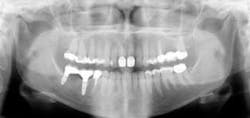

The preceding characteristics are often negated when some other conditions are considered. The factors described in the following discussion may override apparently adequate tooth structure remaining and indicate post placement is required (see Figs. 1 and 2).